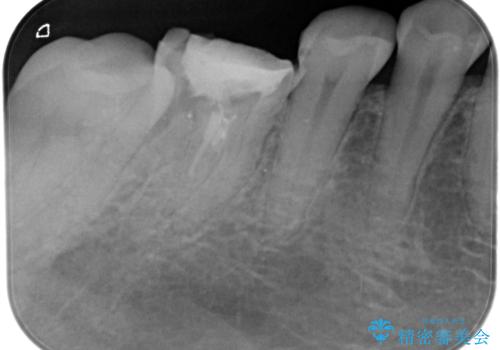

根管内を見てみると、近心根は本来の根管とは違うところを削られて髄床底でパーフォレーションを起こしていました。

また、遠心根でも本来の根管とは逸脱した方向に根管形成されていましたが、修正し充填を行っています。

パーフォレーション部位に関しては、口腔内との交通がなければMTAセメントを用いて修復することで、高い予知性を期待できます。